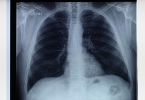

肺结核合并糖尿病的检查需要综合多种方法,以准确诊断和有效治疗。肺结核和糖尿病双重疾病的诊断和管理需要特别注意,因为两者相互影响,增加了治疗的复杂性。1、肺结核的检查方法: 胸部X光检查:这是初步筛查肺结 ...